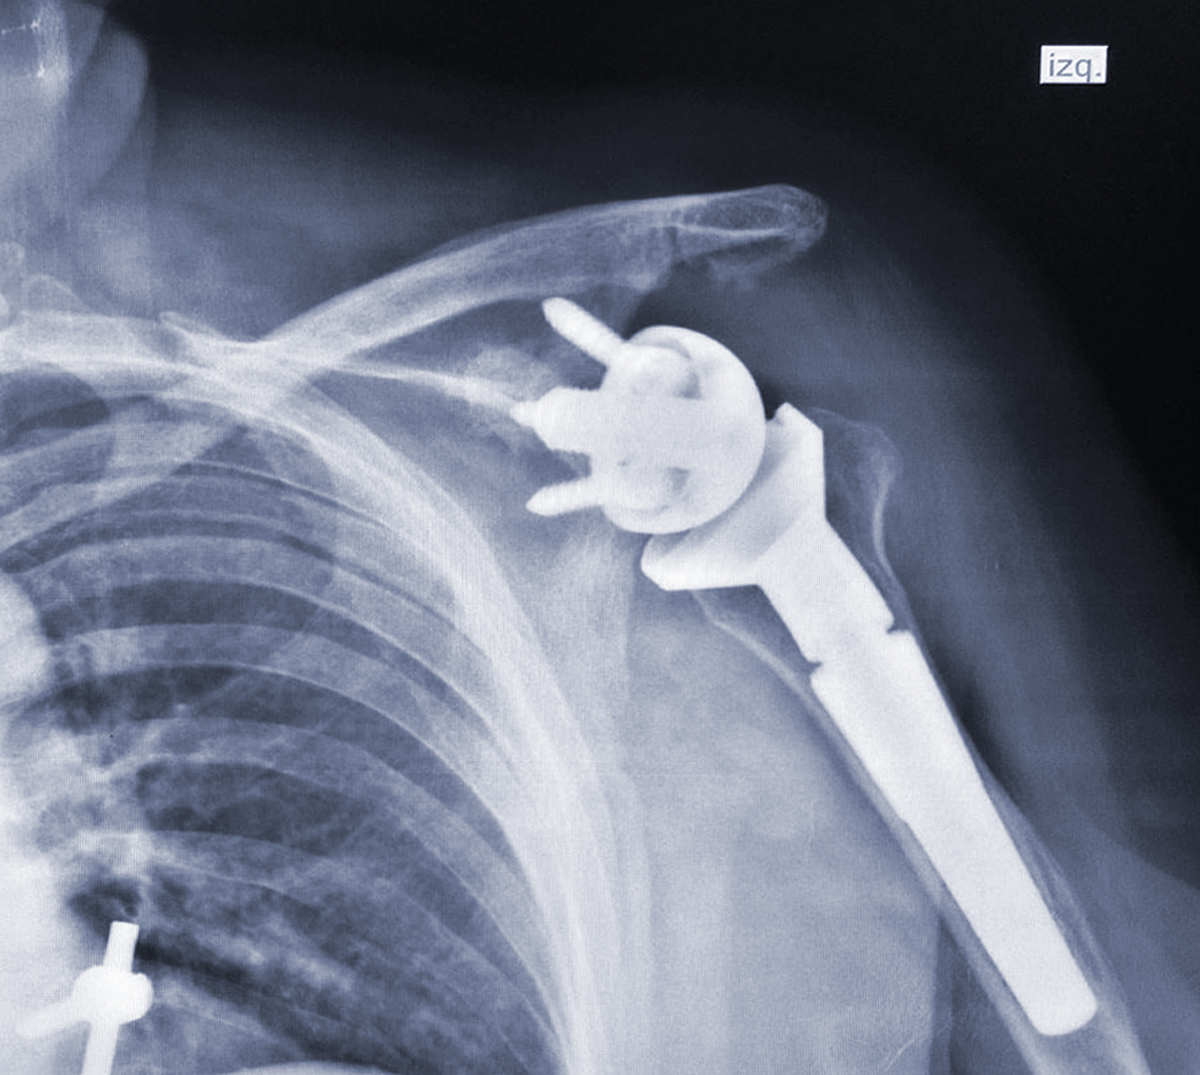

REEMPLAZO ARTICULAR

(HOMBRO, RODILLA Y CADERA)

Las prótesis son implantes ortopédicos que se colocan en el cuerpo con la finalidad de sustituir a una articulación lesionada.

De forma común, sus indicaciones son por secuelas de osteoartrosis, artritis reumatoide y fracturas en algunos casos.